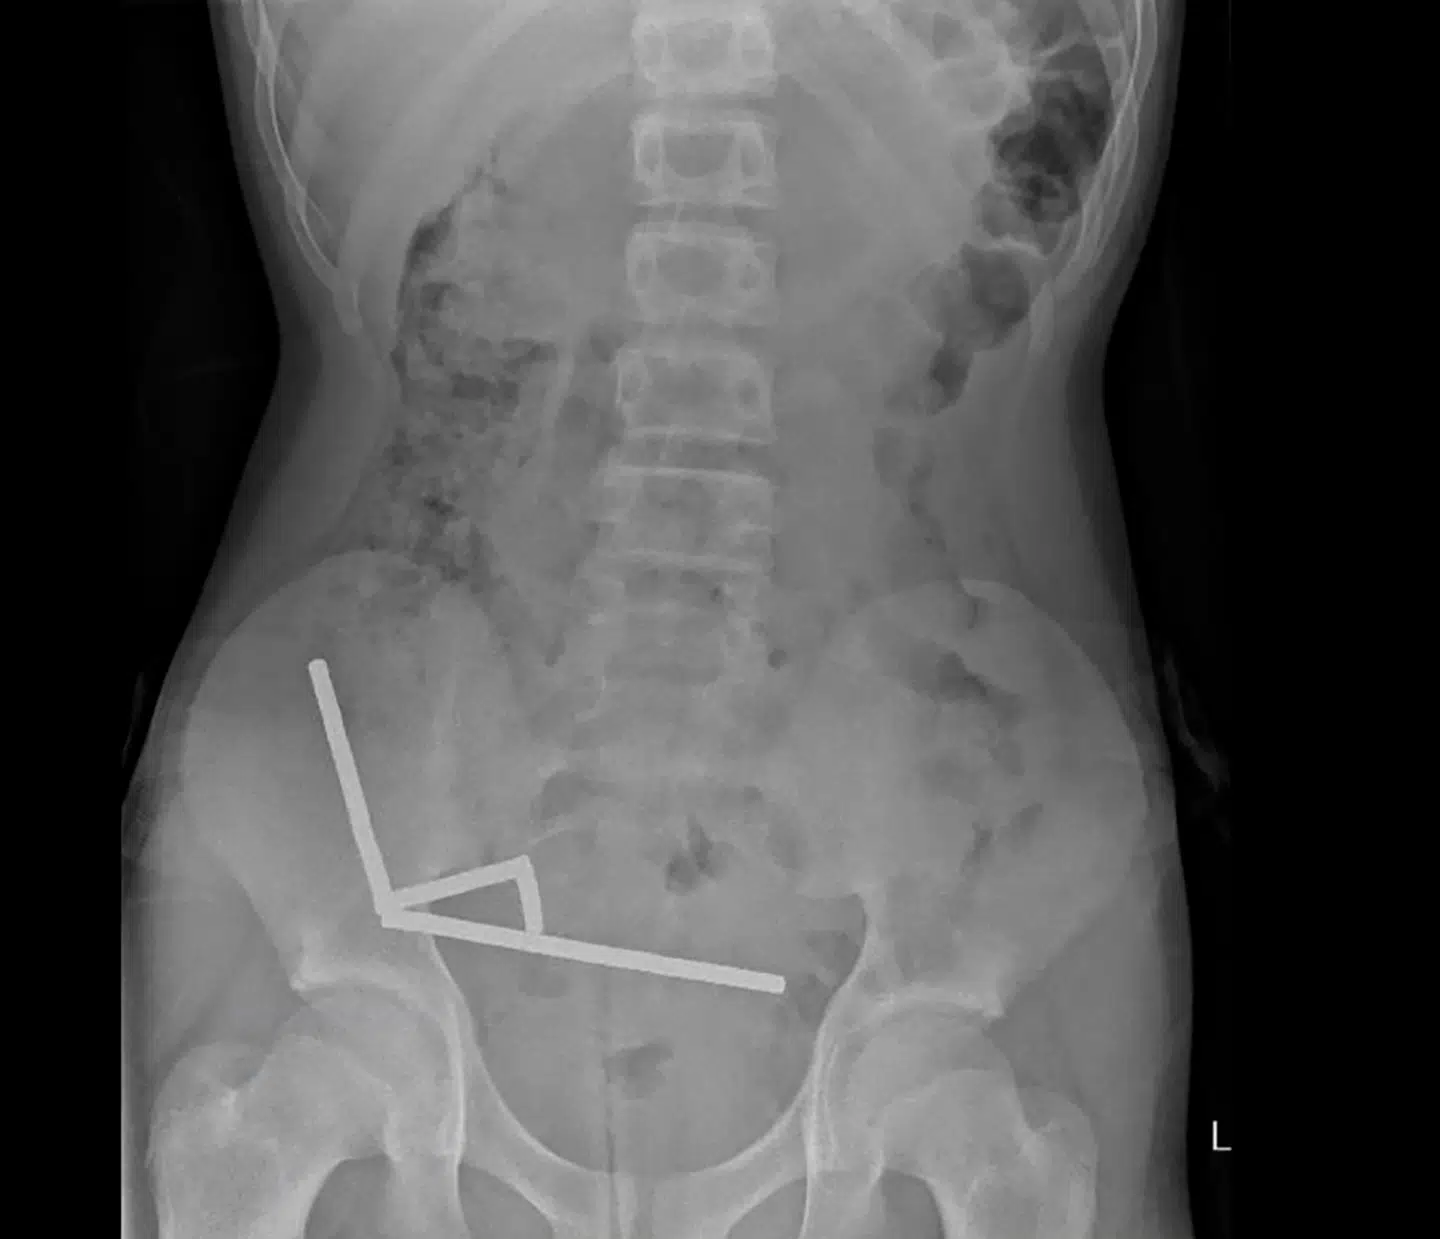

For i maven på den 13-årige dreng fra New Zealand kunne lægerne se fire lige linjer i hans tarme.

»De så ud til at være i separate dele af tarmen, der var klæbet sammen på grund af de magnetiske kræfter,« lyder det i en lægerapport om sagen fra New Zealand Medical Journal, skriver både AFP og ABC News.

I lægerapporten fremgår det, at trykket fra magneterne havde forårsaget nekrose – vævsdød – i fire områder af drengens tyndtarm og blindtarm, som er en del af tyktarmen.